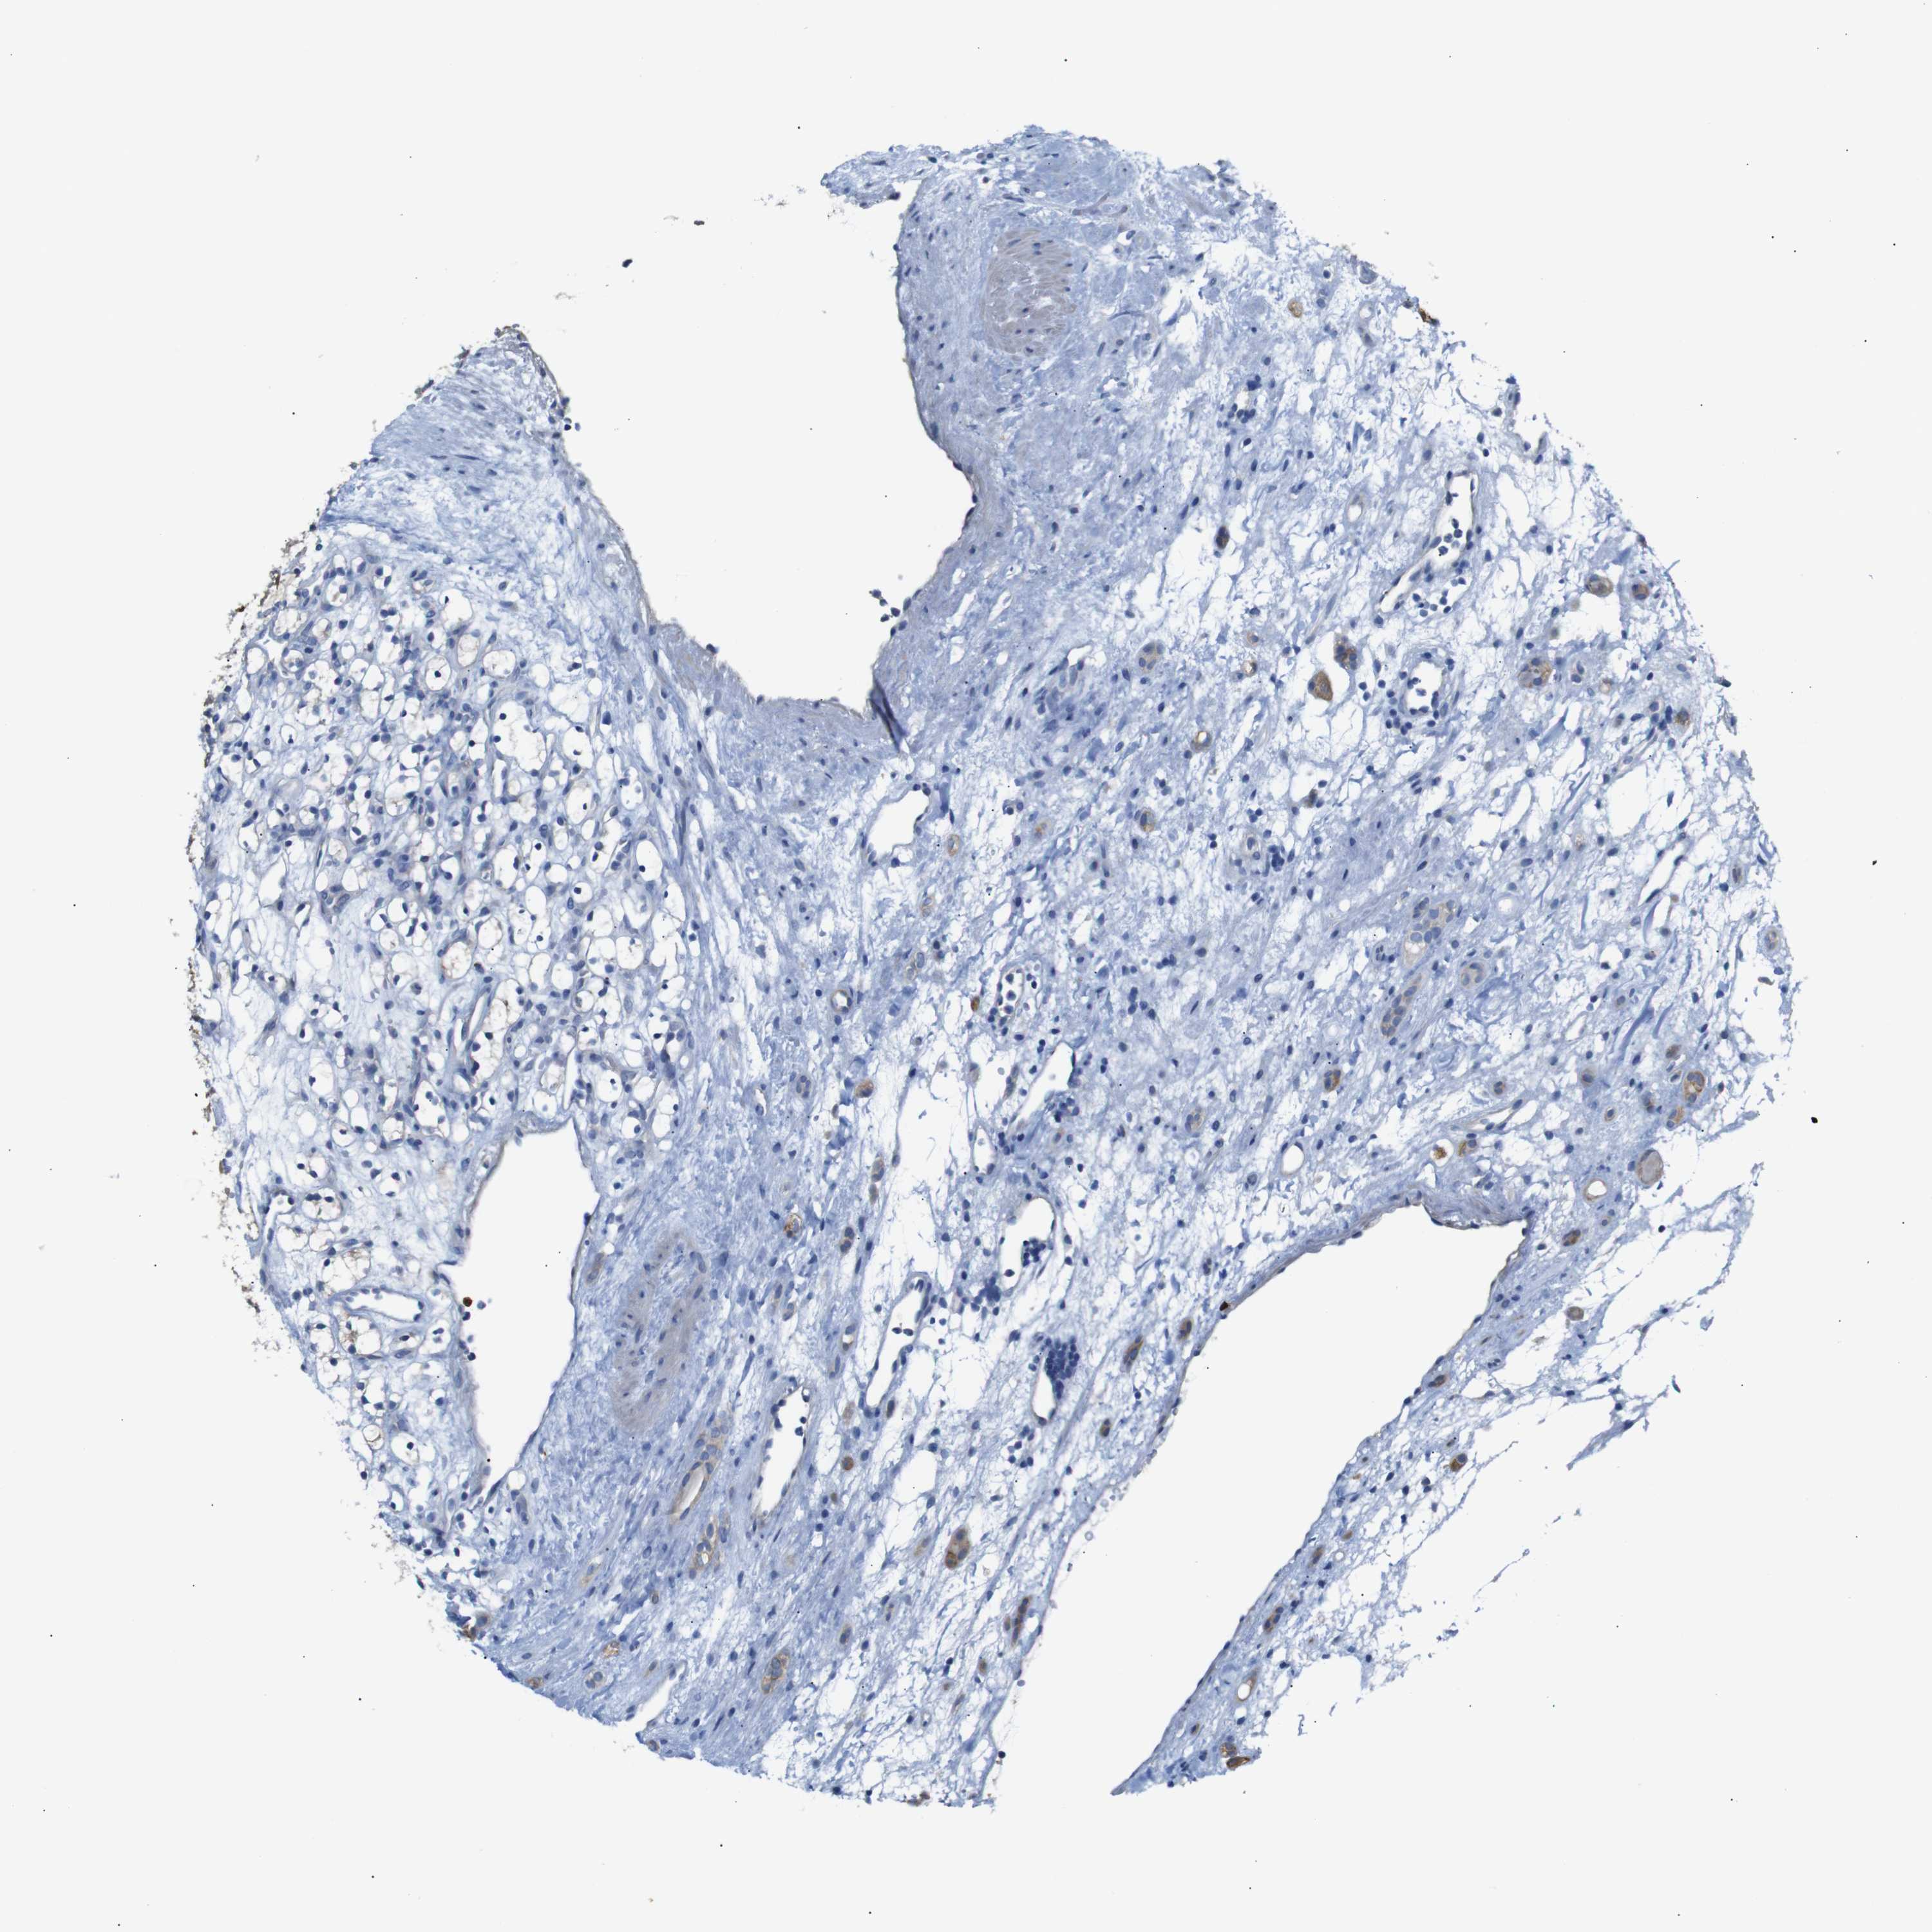

CANCER RENAL CANCER Show tissue menu

KICH TCGA KIRC TCGA KIRC VALIDATION KIRP TCGA PROTEIN RCC CPTAC PROTEIN EXPRESSION